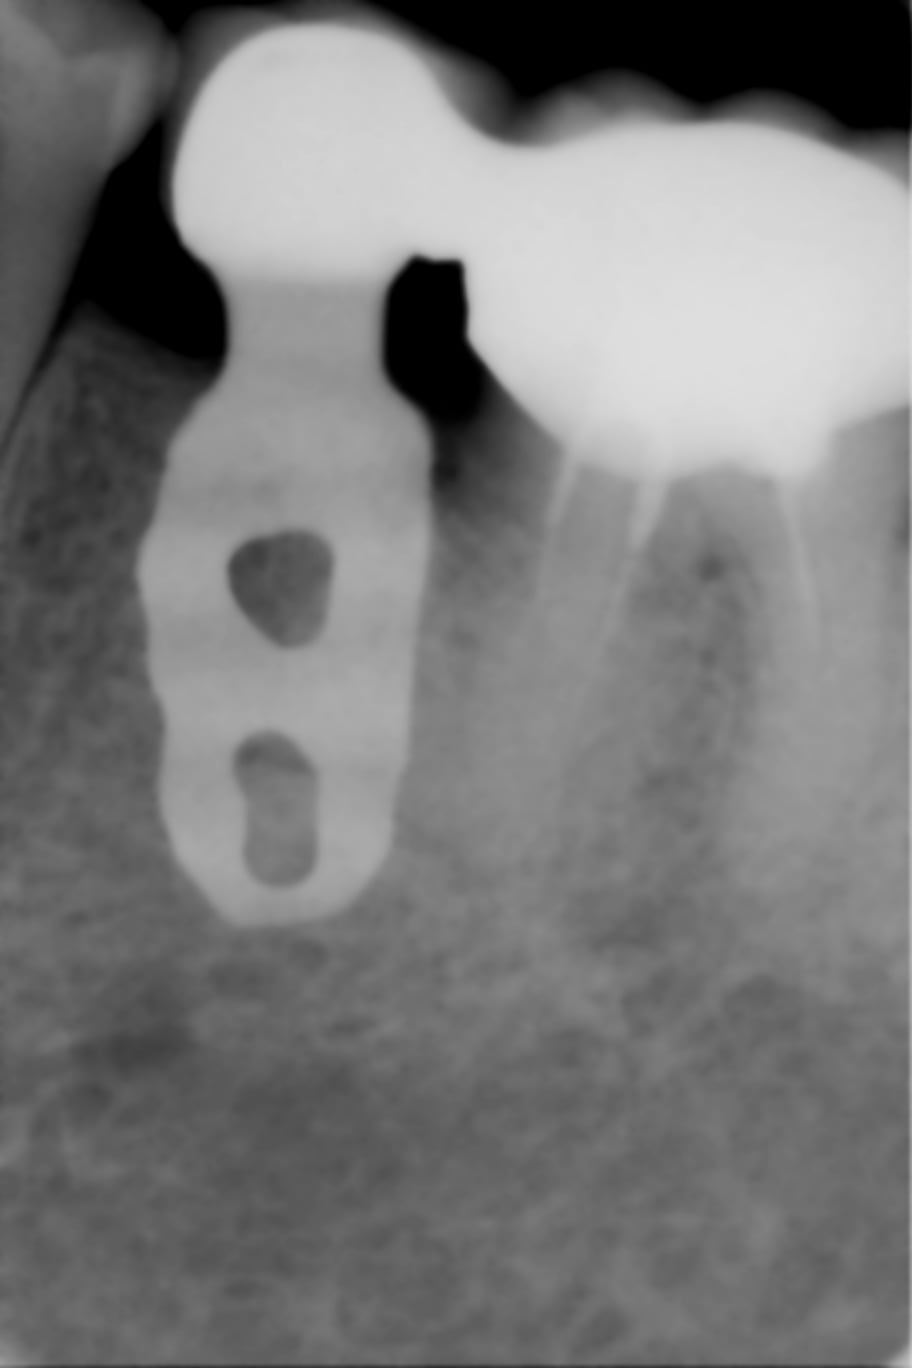

Couronnes solidarisées implanto-dento-portées, réalisées au début des années 90.

Aucun problème pendant 25 ans ....

Vous noterez la qualité du TE 36 ....

C'est quoi comme Implant Gary ? Un petit Implant Lame mais de qui ? C'est du Linkow aussi ? Comme quoi ça tient bien !!!